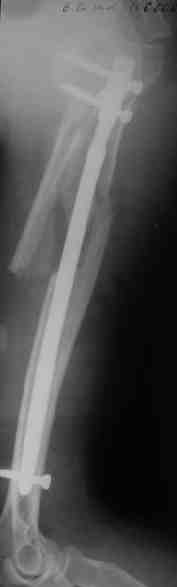

Прооперировали больную с переломом плеча все же гвоздем, Фото в приложении.

Интересно, а канал рассверливали?

Гвоздик похоже ЦИТОвский?

> Интересно, а канал рассверливали?

минимально

> Гвоздик похоже ЦИТОвский?

точно

Немножко уточню ответы Максима.

Только сформировали канал в головке. Диафиз не рассверливали. Хотя при необходимости, конечно, рассверлили бы.

НЗ> Гвоздик похоже ЦИТОвский?

Гвоздь большеберцовый нашей модификации, действительно, их делает предпричятие "ЦИТО". Тут взят 9 мм, укорочен до 240 мм, сделано дополнительное отверстие самое проксимальное, ну и для дистального винта.

Неврологии нет, а выписать можно хоть на второй день, швы можно снять и в местной больнице.

Почему так надолго? На ближэайшие недели - разработка движений, и все. Полагаю, что недель после 4 никаких рекомендаций не будет нужно, просто жить обычной жизнью сельской пенсионерки.